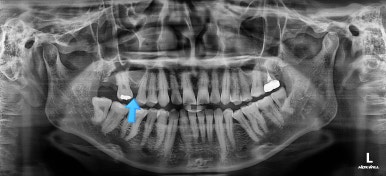

초진 때의 사진입니다.

제일 하단의 X-ray에서 문제점이 보이는데요.

해당 부분의 어금니가 1개가 없었어요.

어금니가 없어진지 꽤 시간이 흘렀기 때문에 몇 가지 문제점이 나타나는데요.

치아가 없는 자리에 바로 임플란트가 불가능합니다.

치아를 뽑자마자 임플란트를 했다면 치료는 간단했겠지만 이번의 경우는 시간이 오래 지나서 뒤쪽 어금니가 발치된 자리로 쓰러졌어요.

앞쪽 치열들도 발치된 자리로 조금씩 이동하는 바람에 틈새가 듬성듬성 생겼어요.

경우에 따라서는 맞물리는 치아(이번 환자분 경우 아랫니)가 솟구쳐 오르면서 어금니 교합이 망가져요.